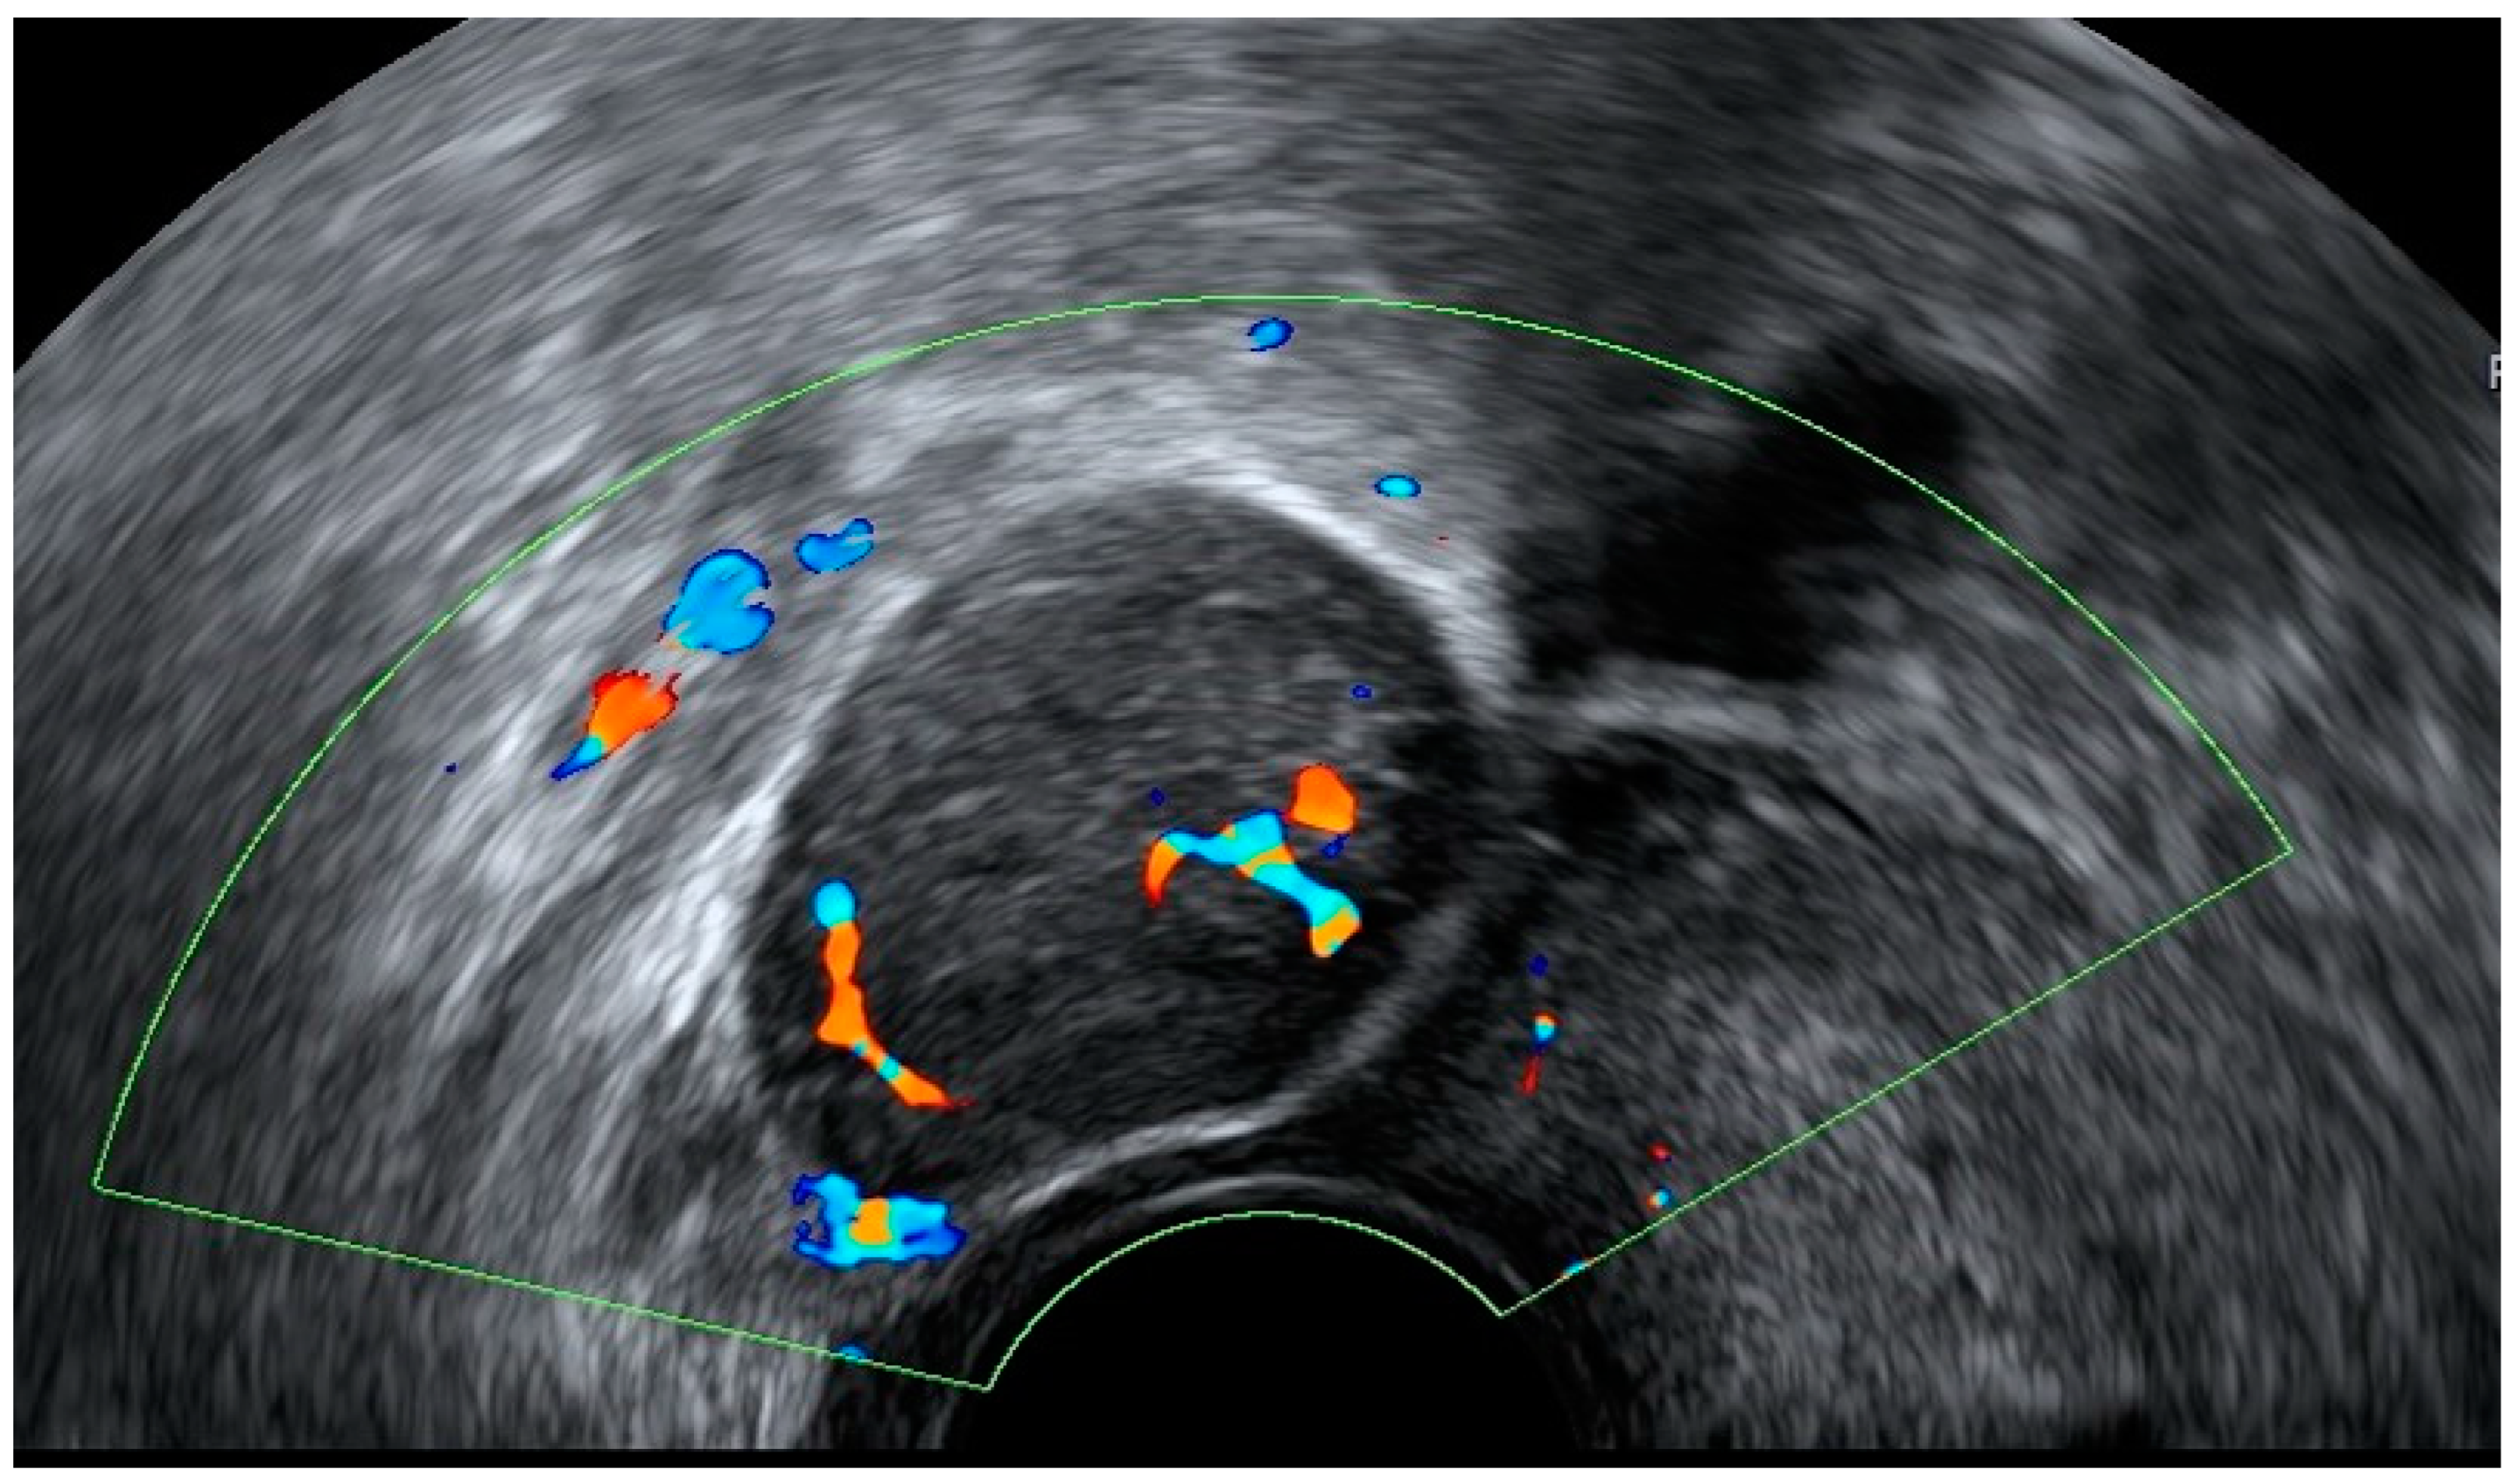

4.1. Pelvic Congestion